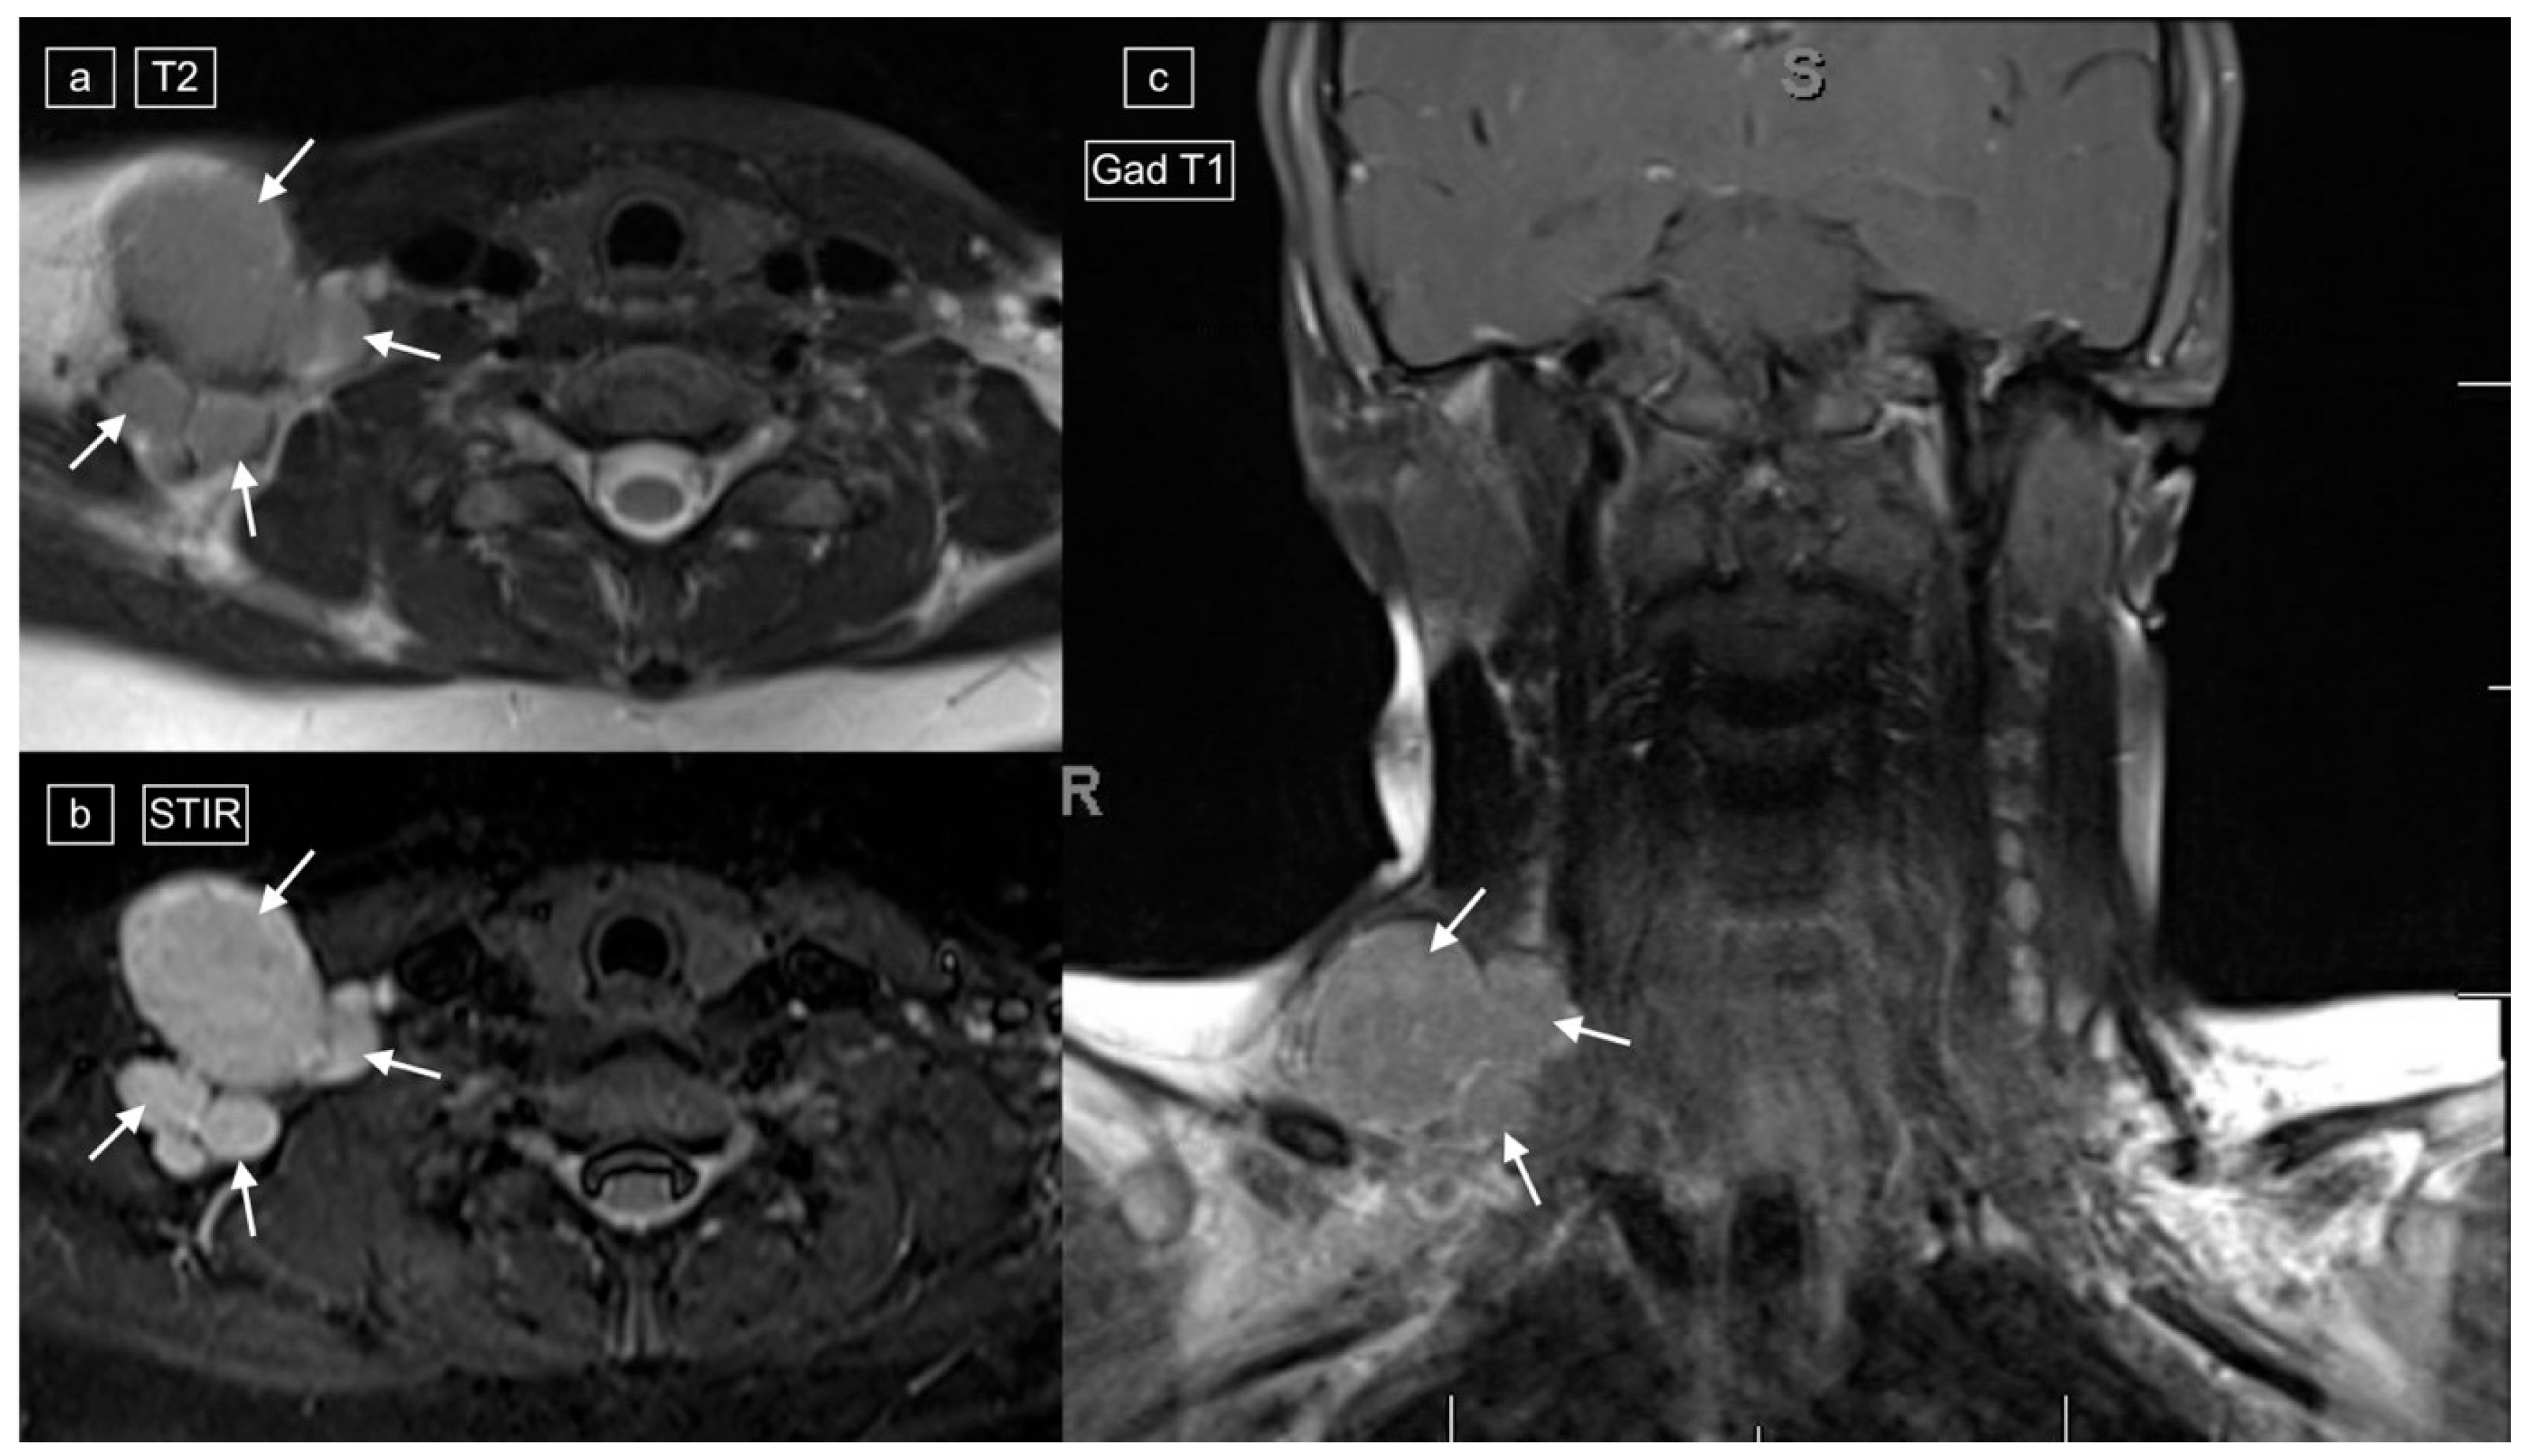

Figure 3.

Images demonstrating technical reasons for lower T2 signal of lymphadenopathy. MRI of the neck and superior mediastinum on coronal T2 with (a) a repetition time (TR) of 4830 and (b) a TR of 5720 [fat-suppressed sequence] in a 14-year-old male with a histologic diagnosis of nodular sclerosing Hodgkin lymphoma. The left cervical and mediastinal lymphadenopathy (straight arrows) show significantly lower signal with lower TR images (a), but even on the higher TR images, central foci within the pathological lymph nodes demonstrate low signal (curved arrows).